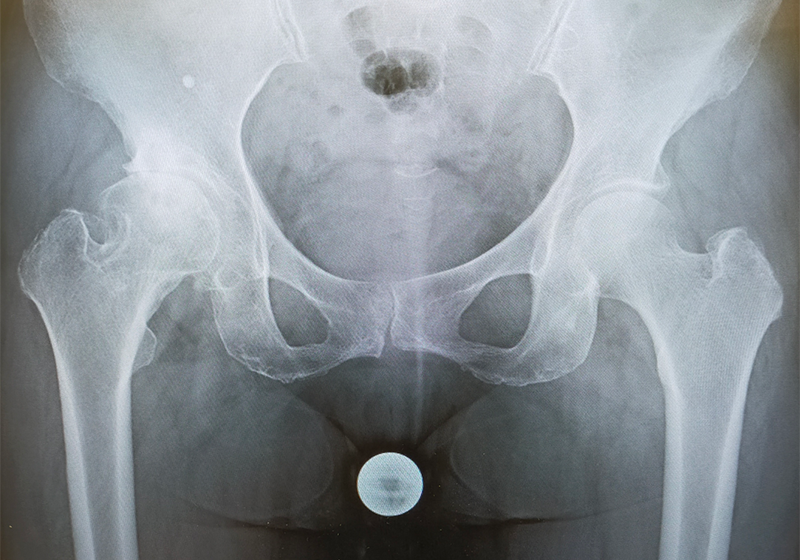

〈手術前のレントゲン〉

当院にて人工股関節全置換術(THA)を施行。アプローチはAMIS(前方最小侵襲手術)で行い、術中に神経ブロックを行い術後の痛みをコントロール、術翌日から歩行器での歩行訓練を開始し術後2日目には杖なしでの歩行が可能となり、スムーズにリハビリを進めることができました。